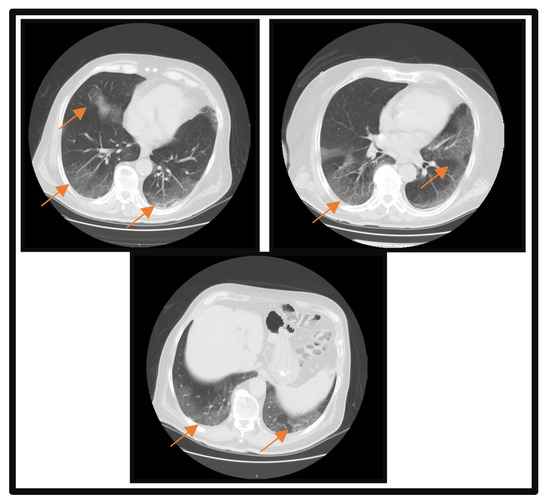

2. Case Report